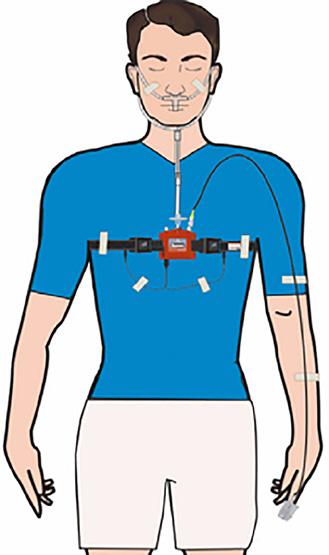

SASO

• Senzori de Laborator

• Rapoarte clare

• Oximetria

• Ritm cardiac

• Sforăit

• Efort Abdominal (Rip Chest Effort)

• Flux de aer (Flow)

• Poziţia corpului

• Cpap Presiune

Simplu,

și Economic

Ușor

MediByte Junior -

Oxigen Asist - Tel 072 000 8891 - București, str. Călușei, nr. 64, sector 2 oxigenasist.ro www.CpapShop.ro 3.345 € TVA inclus

Braebon Poligraf pentru depistarea